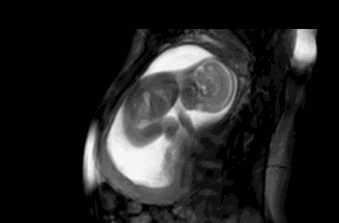

怀孕5个月,胎动很频繁,正常吗

怀孕5个月,胎宝宝大概身长25cm,重320克左右,虽然说还比较小,但胎宝宝已经会学会了很多动作,一些比较敏感、肚子脂肪较薄的准妈妈感觉到胎动频繁也是正常的现象。通常这些准妈妈应该很早就感觉到胎动了。